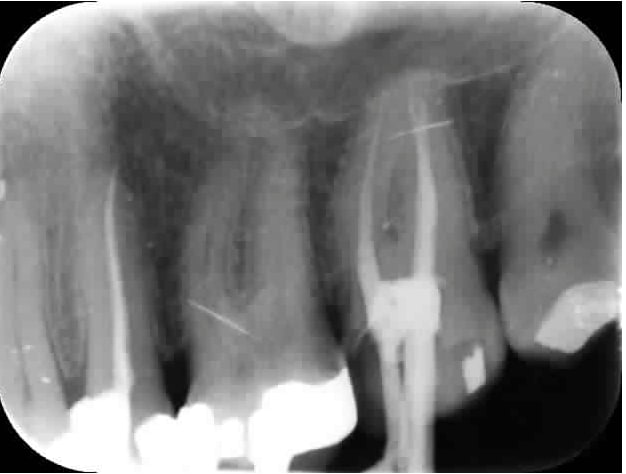

Pèche canal palatin 27. Tant qu'à bien refaire il m'a aussi traité le MV2 qui heureusement pour moi était en Y avec le MV1. -)

Merci David tu relèves le niveau. Au fait tes collègues de promo t'envoient toujours des patients pour faire des RTE et virer les instruments fracturés ? -)

Un truc que je pige pas : la radio de fin de tt endo montrait un canal palatin traité. Comment ne peut on pas s'apercevoir qu'on vire le cone de gutta lors de la réalisation du tenon ? Et pourquoi ce cone s'est barré alors que le tenon n'a pas été réalisé dans la meme séance que l'endo ? Hein ? On a oublié de mettre du ciment de scellement ou celui ci n'a pas pris ?

Pas si pourrie que ca l'endo pourtant au départ à part MV2 non traité. -)